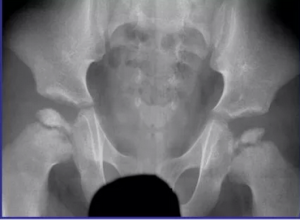

Патология тазобедренных суставов у пациентов с rpl13-ассоциированной спондилоэпиметафизарной дисплазией: результат анализа серии случаев и принципы дифференциальной диагностики с болезнью Легга — Кальве — Пертеса

234567 Ключевые слова: спондилоэпиметафизарная дисплазия; RPL13; болезнь Легга — Кальве — Пертеса; тазобедренный сустав; дифференциальная диагностика